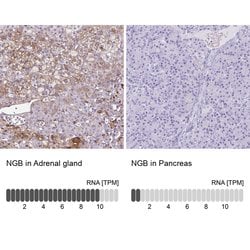

Invitrogen™ NGB Polyclonal Antibody

Globins are a superfamily of gas-binding heme proteins that are present in bacteria, protists, fungi, plants and animals. Globins play evolutionarily divergent roles which include binding, transport, scavenging, detoxification, and sensing of oxygen, nitric oxide and carbon monoxide. Neuroglobin (Ngb) is a hexacoordinate hemoglobin that is predominantly expressed in the vertebrate brain and may enhance oxygen supply to neural components. Neuroglobin displays a high affinity for oxygen and its presence in cerebral neurons suggests a role in neuronal responses to hypoxia or ischemia. For example, in vitro neuronal hypoxia causes an elevation in the levels of neuroglobin, which enhances neuronal cell survival. The human neuroglobin gene maps to chromosome 14q24 and encodes a 151 amino acid protein.

| Immunohistochemistry (Paraffin) | |

| Human | |